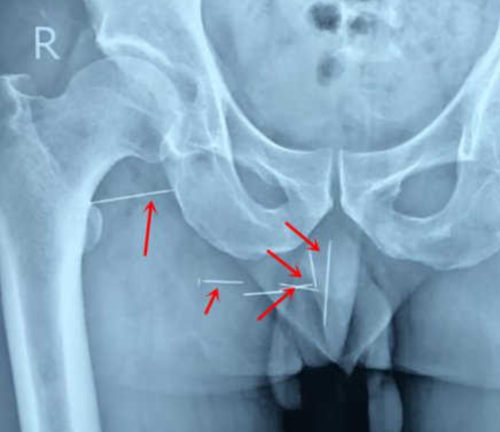

Fyrr í þessum mánuði ákvað hann þó að fara á spítalann til að grafast fyrir um orsök verksins. Röntgenmynd sýnir átta nálar sem grafnar eru djúpt í hægri rasskinn. Chen mundi að hann hefði dottið á ruslahaug í vinnunni og gott ef það voru ekki einhverjar nálar úr málmi þar. Hann plokkaði þær sjálfur úr og hélt hann hefði náð þeim öllum. Það var þó ekki raunin.

Sumar nálanna voru fastar í virkum vöðva sem orsakaði skarpan sársauka þegar Chen hljóp eða teygði á. Chen fór í aðgerð til að fjarlægja nálarnar og tók aðgerðin fjórar klukkustundir.